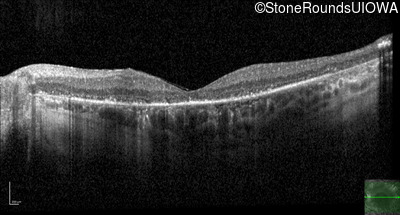

Age at visit: 59 years

This 59 year old woman has been night blind for as long as she can remember. She first noted constricted visual fields in her late 30s.